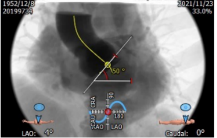

主动脉CT

瓣环平均直径:22.9mm

左室流出道平均直径:23.2mm

瓦士窦大小

横位心:50度

主动脉弓部角度平缓

入路条件尚可